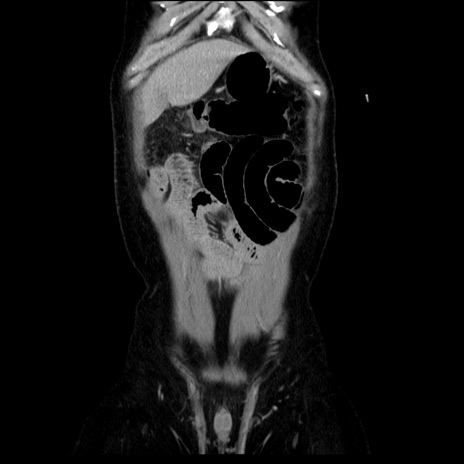

横断像

【症例】40歳代男性

【現病歴】2日前から胃痛あり。徐々に周期的な激痛に変化した。本日になっても激痛があるため受診。

【身体所見】意識清明、BT 38-39℃台あり、腹部:膨満、やや硬、右下腹部に圧痛あり。

【データ】WBC 8500、CRP 23.26